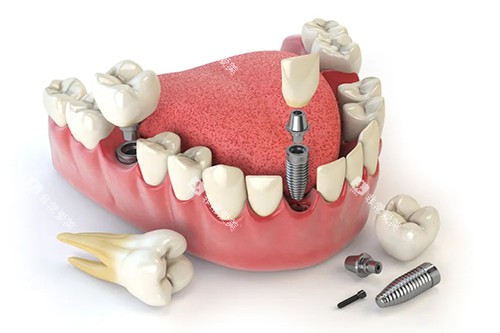

例如,在牙齿种植领域,医生们能够根据患者的口腔状况和身体条件,制定个性化的种植方案,确保种植结果的稳定性和美观性。